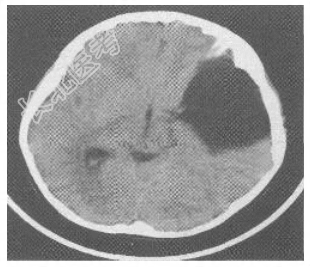

患儿男性,9岁。因“反复头痛半年,加重1天”入院。缘于入院前半年无明显诱因出现阵发性头痛,以左侧颞部明显,呈闷痛样性质,未向他处放射,每次持续约数分钟至半小时不等,尚可忍受,休息后可缓解,无发热、呕吐、四肢抽搐,无偏瘫、失语、智力异常等,未重视未诊治。1天前上述症状加重,部位及性质同前,发作更为频繁,无法正常学习、生活。病程中,食欲尚可,二便正常。体格检查T36.7℃,P98次/min,R20次/min,BP96/58mmHg。神志清楚,言语清晰,对答可,记忆力、定向力、反应力正常。头围54cm,头颅外观无畸形。双侧瞳孔等大等圆,直径约3.0mm,对光反应灵敏,双眼各向活动正常。双侧额纹对称,口角无歪斜,伸舌居中。颈软,心肺腹部查体无明显异常,四肢肌力及肌张力正常,双侧病理征阴性,脑膜刺激征阴性,小脑征阴性。辅助检查头颅CT平扫(图6-38)提示左侧颅中窝蛛网膜囊肿。头颅MRI平扫(图6-39)提示左侧颅中窝占位性病变,大小为8.0cm×6.5cm×6.4cm,考虑蛛网膜囊肿。

图6-38头颅CT诊断左侧颅中窝蛛网膜囊肿。